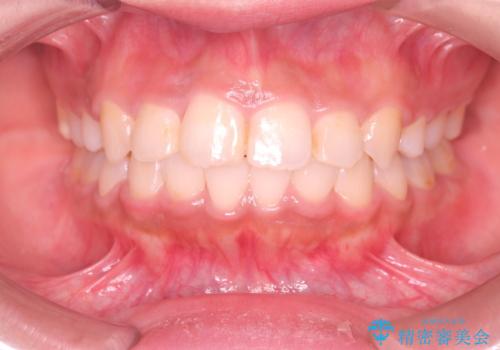

矯正後の後戻り インビザラインで改善

【審美装置】前歯のがたがたを治したい